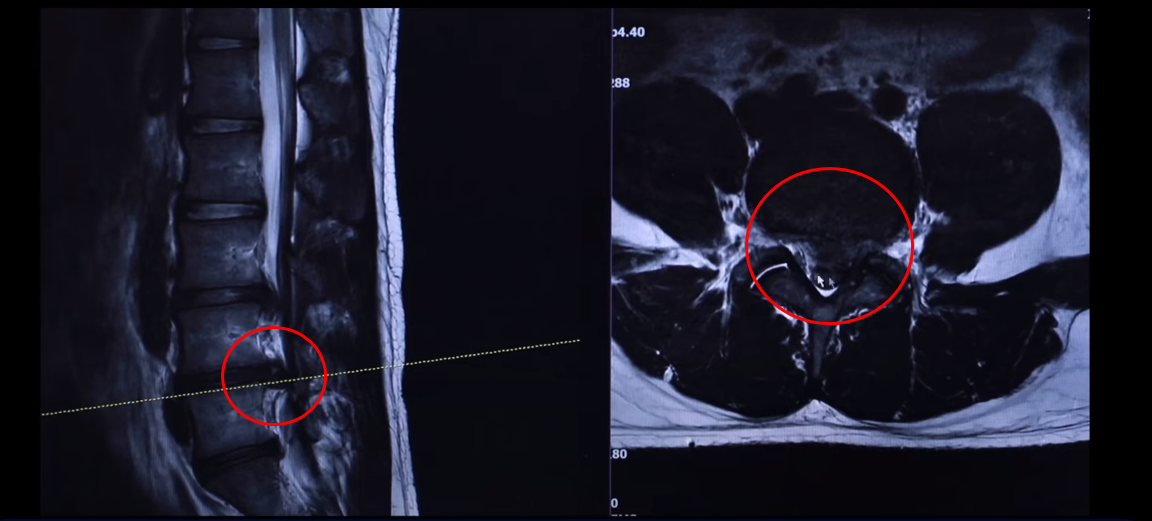

여기 24세 남자 환자분 MRI 보도록 하겠습니다. 옆에서 보는 MRI 보시다시피 어마어마하게 지금 심하게 터져 있습니다. 일반인이 보셔도 아실 정도로 두 마디가 아주 심하게 터졌고 여기도 약간 밀려 나와 있습니다.

단면을 한번 보도록 하겠습니다. 여기를 잘라서 본 단면인데요. 왼쪽으로 많이 밀려 나와 있죠? 이 한마디만 해도 파열돼서 상당히 많이 밀려 나온 겁니다. 왼쪽 다리가 저리고 아플 수 있습니다.